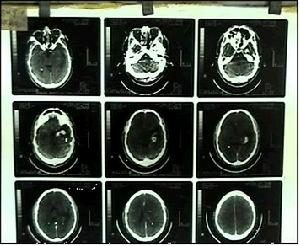

(三)仔細進行神經系統與軀體檢查:有無可疑的陽性體徵,各項輔助檢查(如頭顱平片、腦電圖、顱腦CT檢查,無疑有助於腦瘤診斷,但任何單項檢查均有一定的陰性率,故須結合病史和臨床表現全面考慮,必要時行顱腦核磁共振檢查。成人腦部轉移癌以來自肺、肝、腎、胃者居多,進行相應的輔助檢查。

4.輔助檢查見顱腦腫瘤有關腦腫瘤部分。